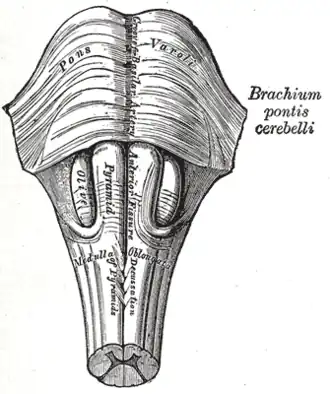

The medulla, showing the olives lying adjacent to the pyramids. | |

The medulla, showing the olivary bodies lying adjacent to the pyramids.

The medulla, showing the olivary bodies lying adjacent to the pyramids. -